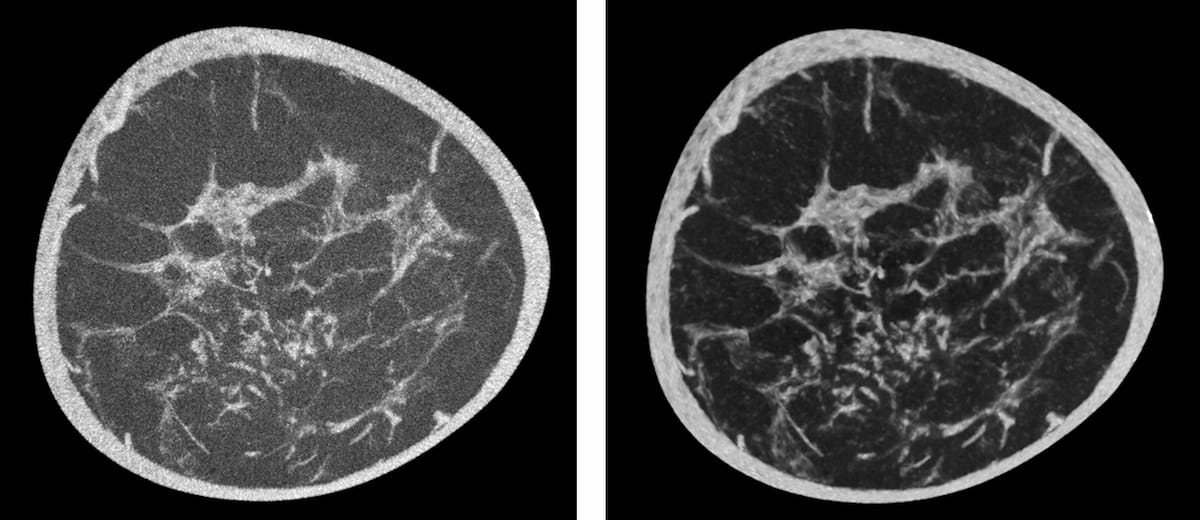

In a study cohort of patients undergoing pre-operative workup for transcatheter aortic valve replacement (TAVR), researchers found the use of photon-counting CT for ultra-high resolution coronary CT angiography had a 96 percent sensitivity rate and an 84 percent specificity rate for the detection of coronary artery disease (CAD).